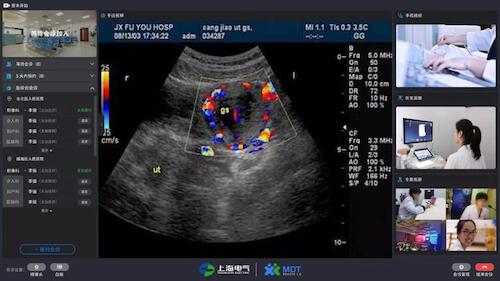

这套名为“MDT1.0多学科远程会诊平台”的5G超声远程会诊系统*基于5G网络技术开发,基本解决了基层医院超声检查*疑难病例的会诊问题。在网络连接正常的情况下,医生只要通过一台电脑、一个摄像头、一个耳麦,就能病人进行实时超声远程会诊*,也免去了医生来回奔波于各个病房的烦劳。

专家通过系统大屏幕既能同步看到动态超声图像*,也能看到操作者操作手法并远程指导操作,实现动态超声影像*与远程医学系统结合,打破传统诊断的局限性。

远程会诊对图像传输要求非常高,需要多路、实时、动态的高清影音图像,这一点在以往传统的网络条件下,超声远程是无法真正达到临床专家的要求的。但在5G条件实测下,系统传输延时不到200毫秒,能确保手法视频、超声视频、医生沟通视频及音频的同步性和一致性。